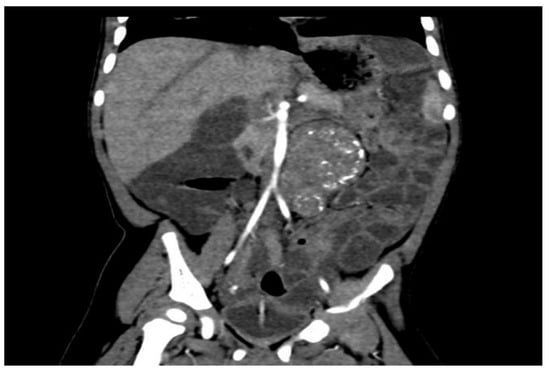

In light of the ongoing significant abdominal distension, an abdominal X-ray was conducted, revealing bowel dilation characterized by air-fluid levels and the absence of any luminal obstructive lesion (Figure 1).

Figure 1.

Radiographic indications of bowel distension with discernible air-fluid levels and the nonexistence of any lesion causing luminal occlusion.